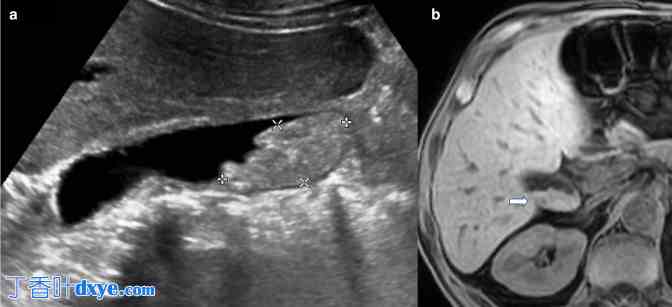

胆囊淤泥模仿胆囊病理。(a)纵向切面的灰阶超声图像显示非移动性胆囊“息肉样肿块”。(b)随后的 MRI 未增强的 T1-VIBE 图像显示胆囊腔内高 T1 信号分层,这是由淤泥中的金属离子引起的顺磁效应的典型特征,没有软组织肿块的证据(白色箭头)。VIBE,容积插值屏气检查